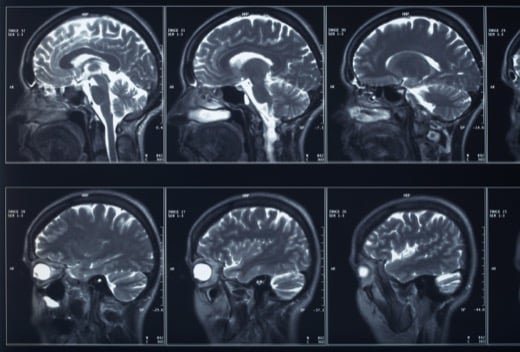

A concussion is a mild traumatic brain injury and should always be taken seriously. When there is a force against the head or a sudden deceleration of the head, your brain moves and hits the inside barrier of your skull. Auto accidents often lead to concussions because people collide with the window, steering wheel, windshield, or ground if they are thrown from the vehicle. Even impacts at lower speeds like 30 mph can result in a significant force on the head and neck, leading to a concussion. If you suffered a mild TBI in a crash, contact the experienced Charlotte personal injury attorneys at Dr Ted Injury Law P.A. for help.

Normally the brain is cushioned by fluid within the skull that allows it to move slightly and remain undamaged from small bumps and blows. However, a strong force causes the brain to move violently back and forth against the skull. This trauma affects how the brain functions for a period of time. It disrupts normal brain activity, which leads to the various symptoms of a concussion.